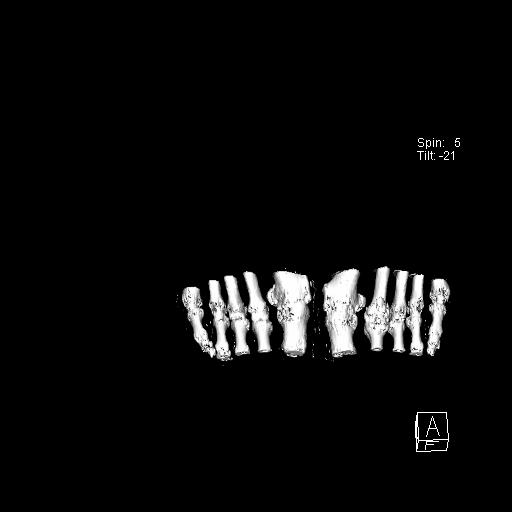

标题: CT13415:M72Y,跖趾关节病变,请会诊 [打印本页]

标题: CT13415:M72Y,跖趾关节病变,请会诊

男72岁左侧跖趾关节肿痛15年,查压痛。